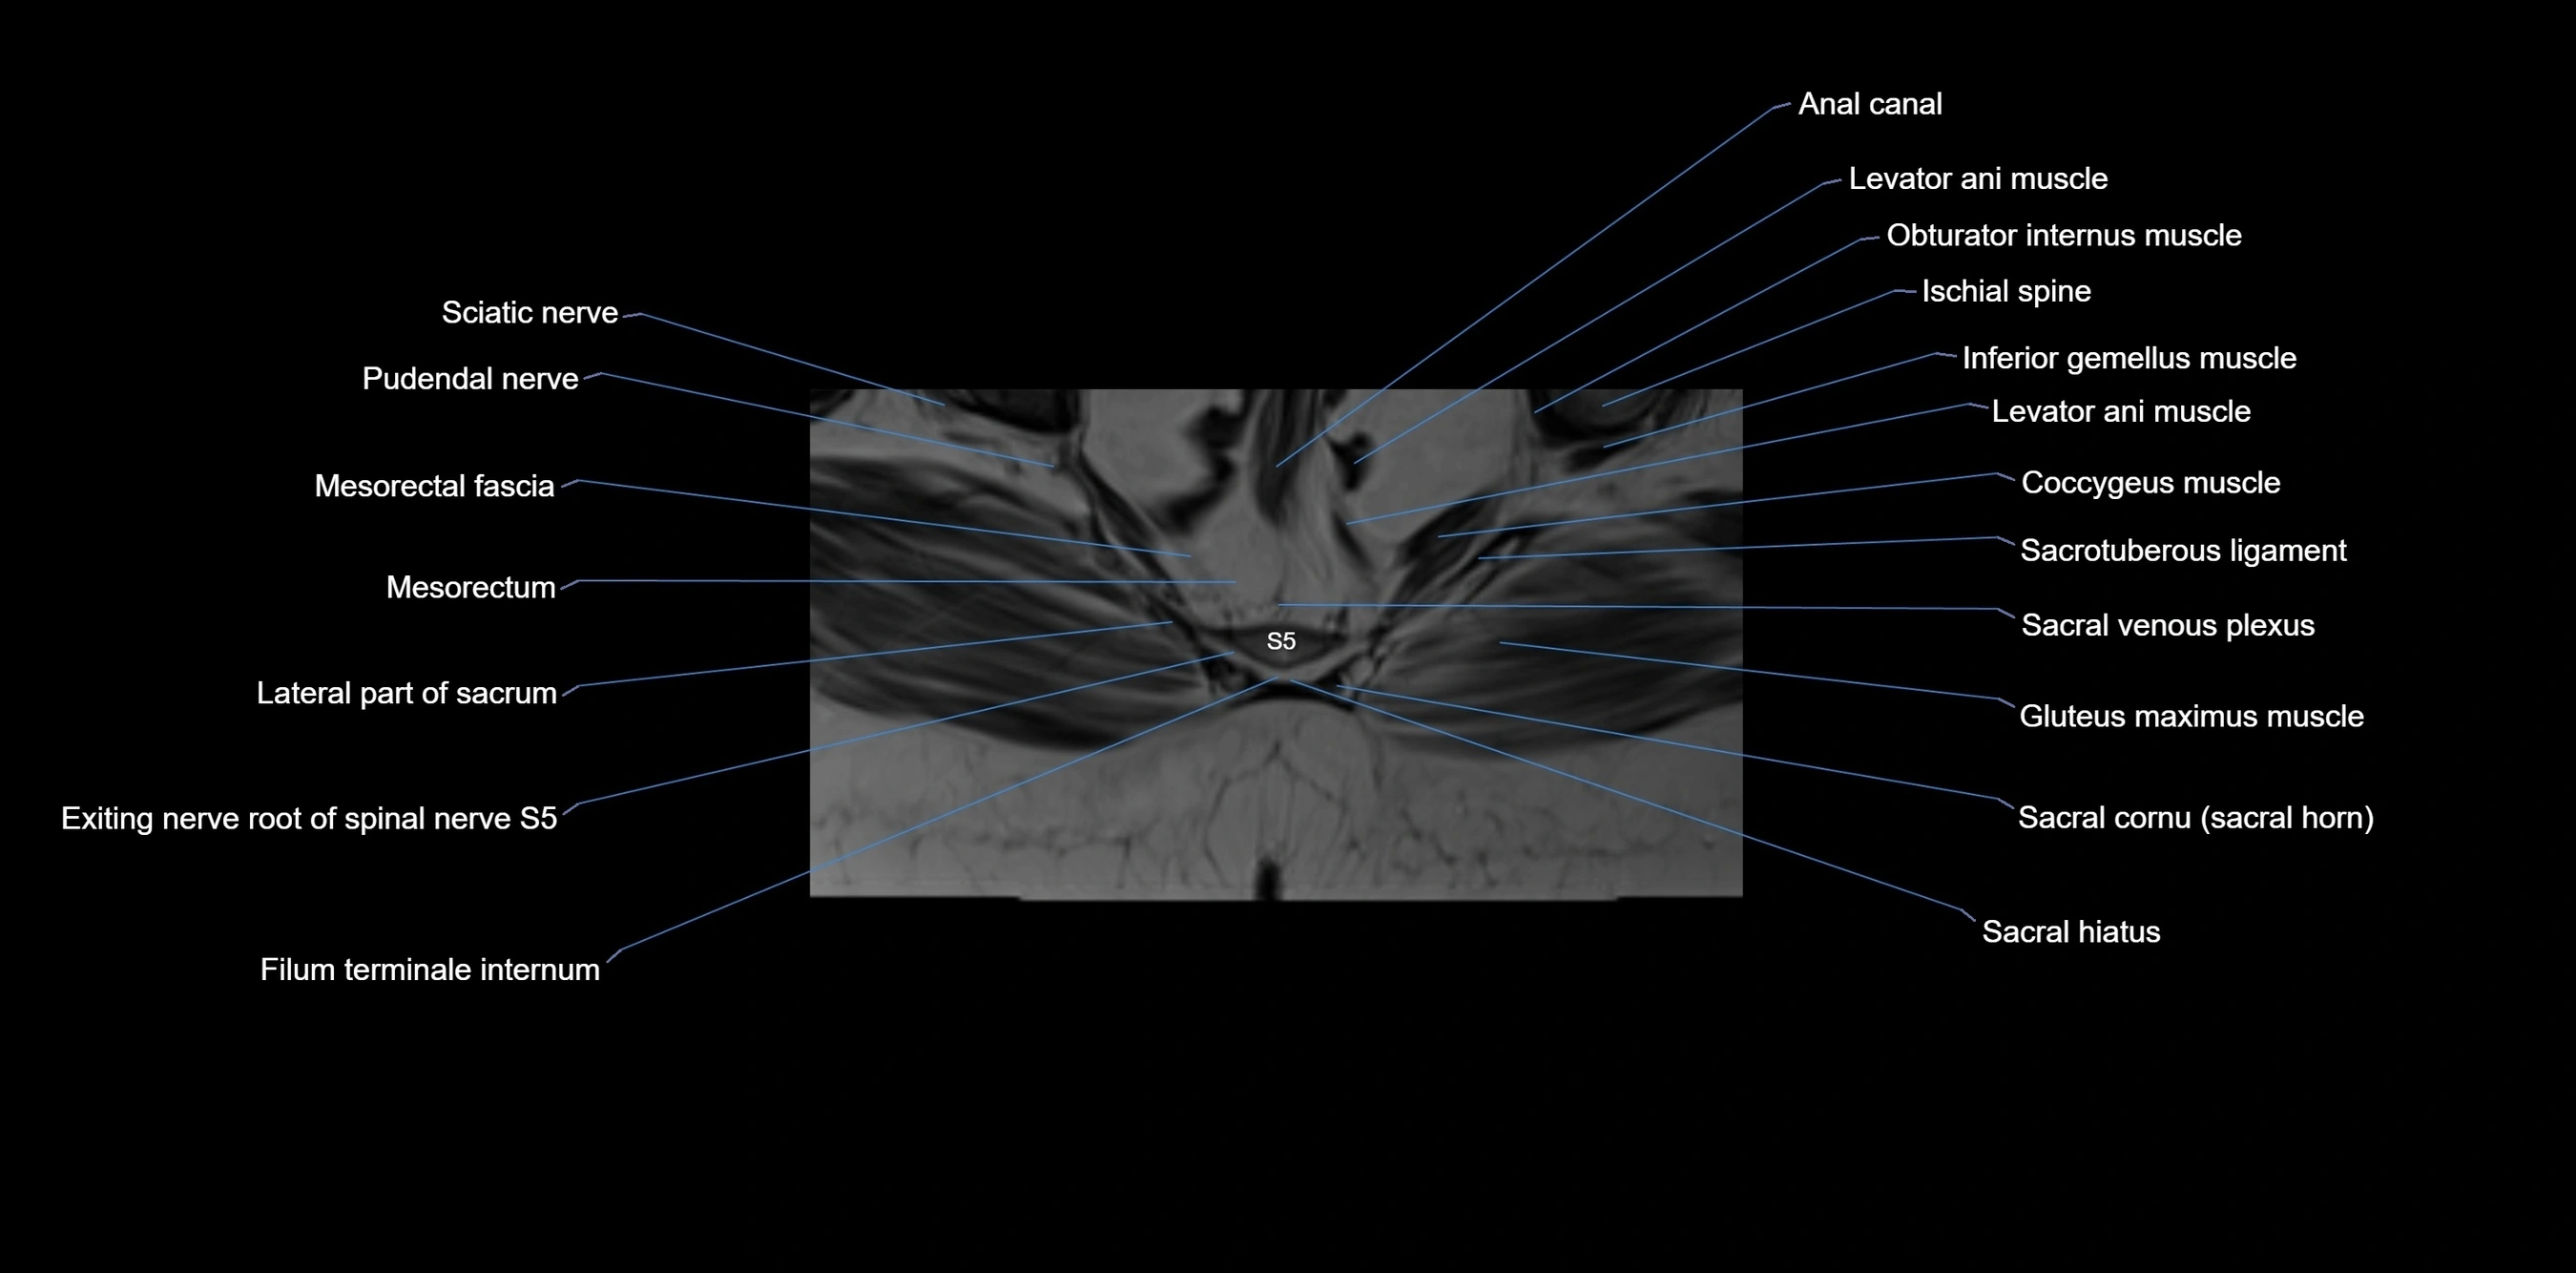

MRI Appearance

T1-weighted images:

• Cortical bone appears very low signal (dark); marrow shows intermediate signal

• Iliac fossa fat is bright against low-signal cortex

T2-weighted images:

• Cortical bone remains dark

• Marrow signal varies depending on fat content; edema or tumor shows hyperintensity

STIR:

• Suppresses fat, making bone marrow edema, fractures, or infiltrative lesions appear bright

• Excellent for trauma, sacroiliitis, and metastatic evaluation

T1 Fat-Saturated (Pre-contrast):

• Marrow: intermediate signal, fat suppressed

• Useful for detecting subtle marrow abnormalities adjacent to iliac cortex

T1 Fat-Saturated Post-Contrast (Gadolinium):

• Enhances vascularized structures, marrow pathology, tumors, and inflammatory changes

• Highlights soft tissue or bone invasion in pelvic neoplasms

MRI Non-Contrast 3D Imaging:

• Provides 3D morphology of iliac wing, crest, and articulations

• Used in preoperative planning for pelvic surgery and trauma reconstruction

MRI image

image